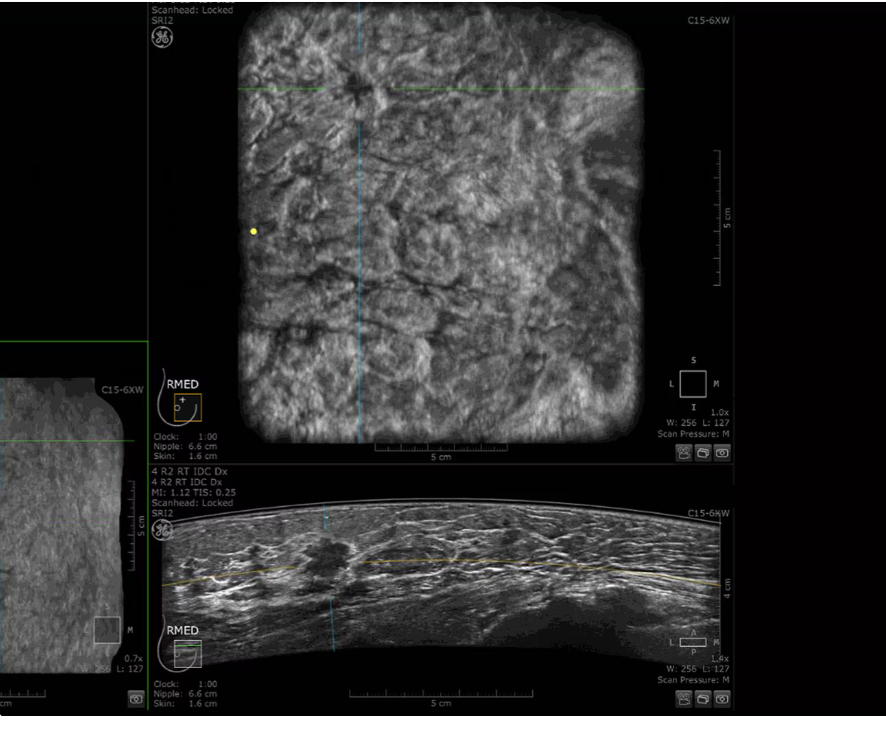

CLINICAL IMAGES

Dense breast tissue and cancer appear white on a mammogram, potentially camouflaging small cancers. Invenia ABUS 2.0, is specifically designed to help clinicians find cancers that may be hidden on mammography.

Lesion characterization for confident staging in dense breasts

Invenia ABUS 2.0 uses the latest ultrasound innovations and AI based solutions to help improve precise diagnosis and elevate clinical confidence.